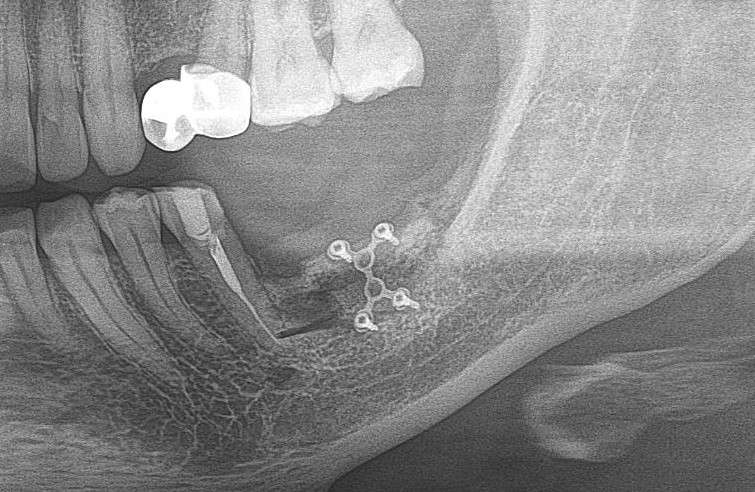

10. Контроль.

После операции мы делаем контрольные снимки. Это может быть ортопантомография:

или конусно-лучевая компьютерная томография. Как вам больше нравится.

Результат остеопластики методом остетотомии мы можем оценить уже через 4 месяца. Перед этим сделаем контрольные снимки (слева «до», справа «через 4 мес»):